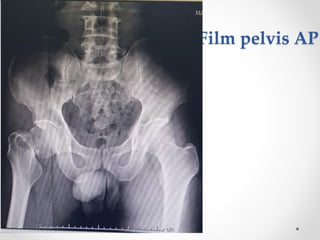

Film pelvis AP

Film Rt.Hip lateral

Film Rt.knee AP-lateral

Film CXR